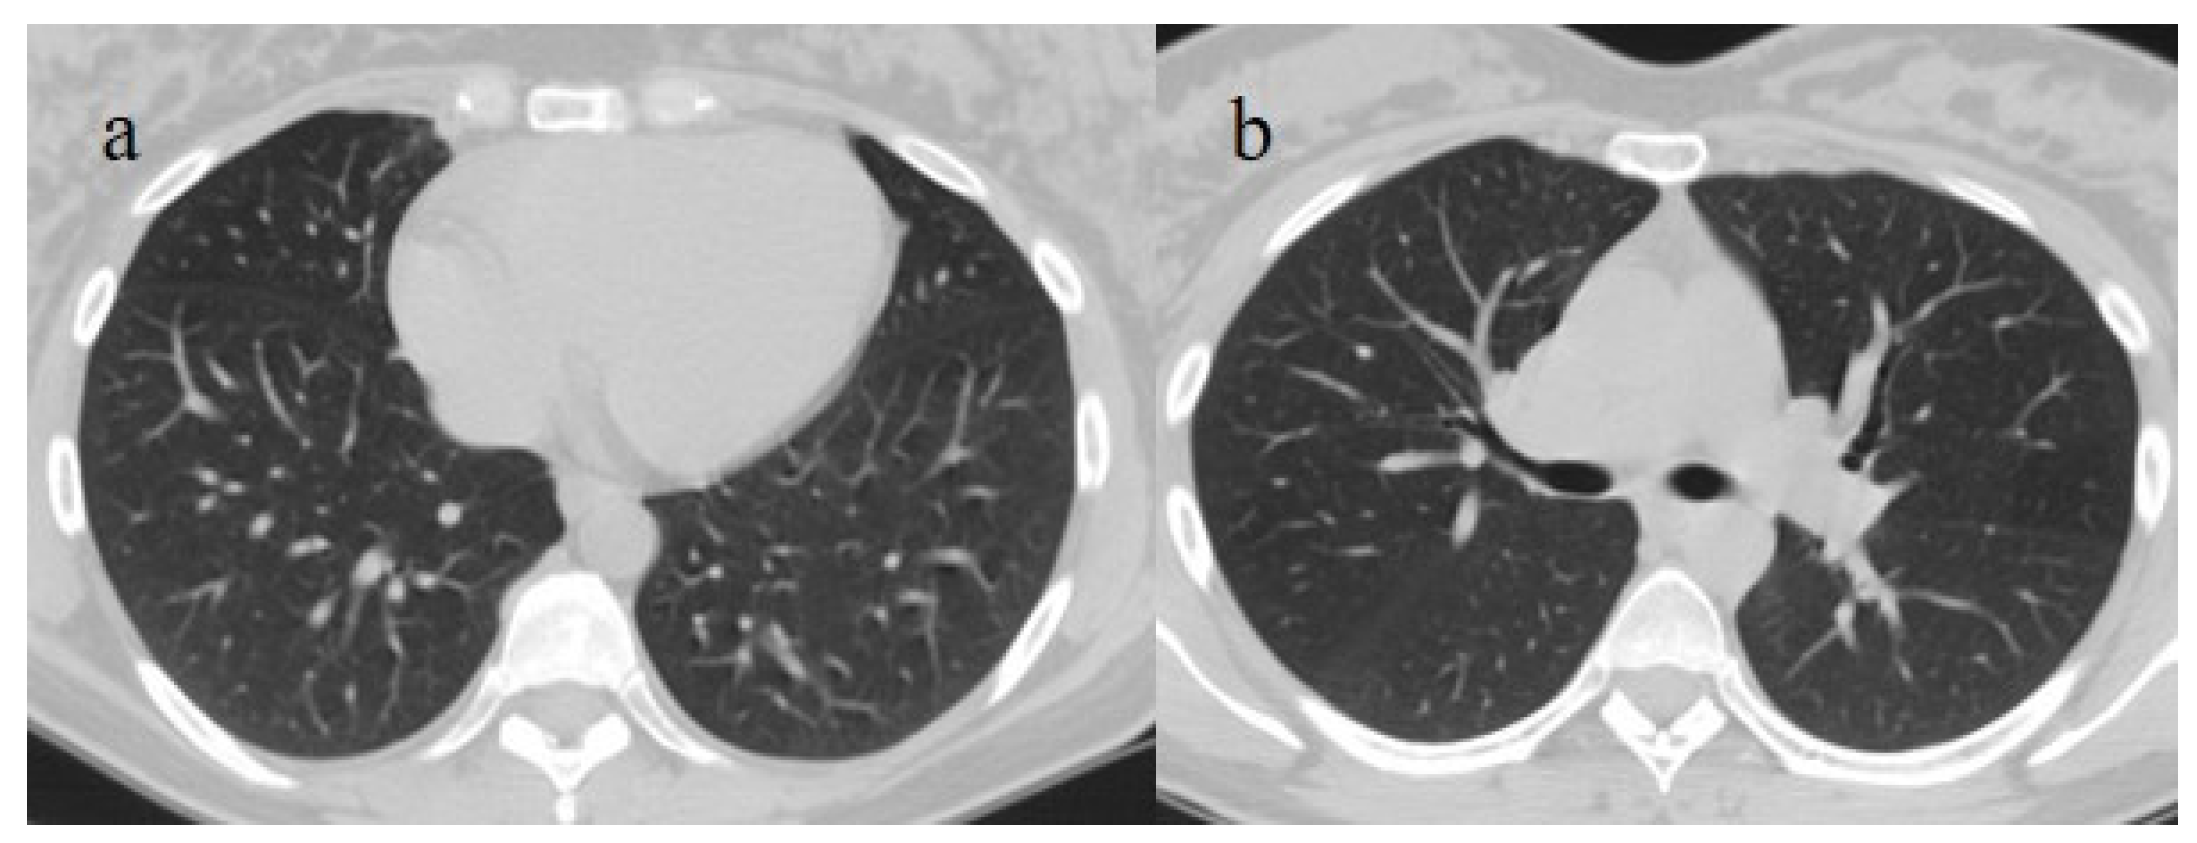

| Typical Appearance | GGOs with a crazy-paving pattern and consolidations in a peripheral and posterior or central-peripheral distribution; multilobar involvement; vascular enlargement, the halo and reversed halo sign; subpleural and parenchymal bands; and architectural distortion. They were predominant since the Delta wave. |

| Indeterminate Appearance | GGOs and consolidations with a unilateral, central, or upper-lobe distribution. |

| Atypical Appearance | Lobar consolidation, lung nodules or masses, miliary patterns, tree-in-bud patterns, cavitation, pleural effusion, central distribution, and lymphadenopathy. Atypical appearances were predominant during the Omicron waves. |

| Typical appearance | From the wild-type to the Delta variant. | Askani et al., 2022 [67] | The Delta variant presented more frequent typical features with more extensive lung involvement than the Omicron variant. The Omicron variant was more frequently associated with the absence of pneumonia. |

| Inui et al., 2021 [68] | Typical findings were characteristic of the wild type to the Delta variant. GGOs with consolidation and repair changes were more frequent in the Delta variant. The Delta variant also showed more rapid pneumonia progression than the wild-type and Alpha variants. | ||

| Ito et al., 2022 [54] | Peripheral GGO distributions were more frequent in the Alpha and Delta variants than the Omicron variant. | ||

| Kirka et al., 2022 [27] | Typical features were found in 40.8% of patients with the wild-type variant and 1.7% of patients with the Omicron variant. | ||

| Lee et al., 2023 [28] | Typical CT patterns were more frequent in the Delta group (76%) than in those with the Omicron variant (42%). | ||

| Yang et al., 2022 [78] | Of patients with the Alpha variant, 86.84% presented typical COVID-19 pneumonia CT features. | ||

| Yoon et al., 2023 [69] | Only 32% of patients with the Omicron variant presented typical findings, compared with 57% of the Delta variant cases. | ||